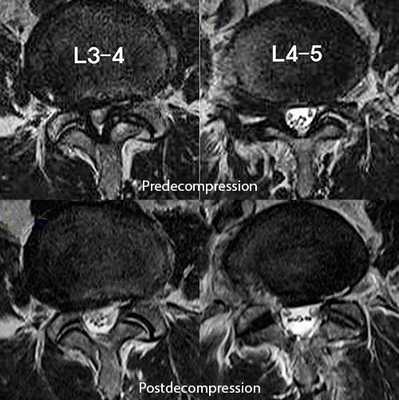

На МРТ поясничного отдела позвоночника показан стеноз позвоночного канала и состояние после операции эндоскопической декомпрессии на уровнях L3-L4 и L4-L5.

Иногда при стенозе позвоночного канала бывает целесообразно разделить операцию на два этапа. На первом этапе выполняется декомпрессия наиболее страдающих корешков спинного мозга, проводится курс интенсивной вазоактивной и нейростимулирующей терапии. И, если не достигнуто улучшение и облегчение состояния больного, можно предложить второй этап операции — более широкую декомпрессию (двустороннюю гемиламинэктомию) и создание дополнительных резервных пространств при стенозе позвоночного канала.